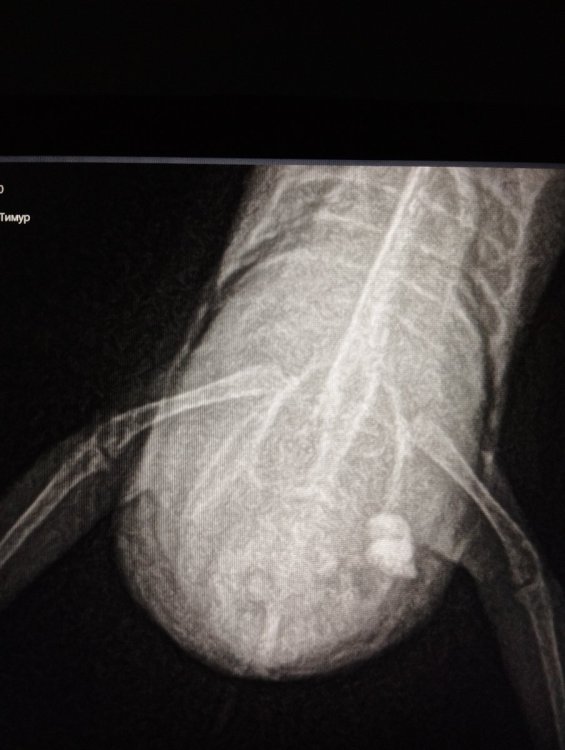

Меньше месяца назад я заметил, что у самки волнистого попугайчика нащупывается что-то твёрдое внизу живота, и заподозрил, что это может быть яйцо. Отнес к ветеринару, который ее прощупал и сообщил, что яйца там нет, и предположил липому или что-то другое, но точный диагноз поставить не смог. Для профилактики он назначил 10-дневный курс антибиотики+витамины в поилку и Ветом-1 в кормушку, и направил на рентген (который я сделал в тот же день). За время курса особо ничего не изменилось, наоборот, низ животика визуально увеличился ещё больше. Я потом сделал ещё один рентген, и снова принёс на осмотр. За это время я тажке прочитал форумы и заподозрил липому, поэтому около 2-х недель назад сменил корм (убрал семена подсолнечника). В последние 10 дней добавляю в кормушку 1 истолчённую таблетку Карсила (35 г), иногда добавляют Ветом-1 и Бифидобактерин (Наринэ), я так понимаю, что вреда от них не будет, в поилку добавляю Элькар (6-7 капель на 50 мл воды). Ветеринар сказал, что хирургическое удаление липомы у волнистого попугайчика - это лотерея, поэтому шансы 50:50, так что это крайний вариант. 1. Вид птицы: волнистый попугайчик. 2. Возраст 5 лет и 6 месяцев, самочка; 3. Рацион: в основном, корма Travel и Коробкофф. Иногда даю морковь (хотя она её в основном просто грызёт) и укроп (просовываю в клетку), к остальным овощам и фруктам птица равнодушна (я так и не смог её к ним приучить). В последние дни даю в основном жёлтое просо (к которому она привыкла), в смеси с овсом. Пытаюсь также приучить её есть варёную гречку, смешанную с тёртой морковью и яблоком, но они едят её неохотно. 5. Температура сейчас около 20 градусов, влажность нормальная, световой день около 17-18 часов (вечером допоздна бывает включен свет). Птичка живет вместе самцом (возраст >13 лет), он здоров и для своего возраста очень хорошо выглядит. Питается сейчас тем же, что и самочка. 6. У птички увеличился низ животика. В остальном птица очень активная, много летает и двигается, когда отдыхает, периодически сидит на одной лапке. Но буквально в последние 2-3 дня стала летать хуже, причём я заметил, что особенно трудно ей бывает летать по утрам. 7. У птички стал быстро увеличиваться низ живота, первые симптомы я заметил в районе 12 сентября, хотя буквально за 3-4 дня до этого все было нормально. Сейчас животик стал ещё больше. 8.1. Есть рентгеновские снимки сверху и сбоку за 13-е (первые 2 р-снимка) и 25-е сентября (вторые два р-снимка). 8.2. Антибиотики+витамины в поилку и Ветом-1 в кормушку - курс был 10 дней, результатов нет. Затем Карсил+Элькар - даю последние 2-х недели, но результаты пока что не очевидны. Хотелось бы понять в первую очередь, точно ли это липома или что-то другое (липосаркома, асцит и т.д.), и что сейчас можно сделать? Продолжать лечение Карсилом+Элькар, или её лечить надо от чего-то другого? Или нести на рискованную операцию? Фото прилагаются (кроме рентгенов за 13 и 25 сентября, остальные фото птицы сделаны сегодня). Если надо, могу добавить ещё фото сделанные в течение последнего месяца.

-